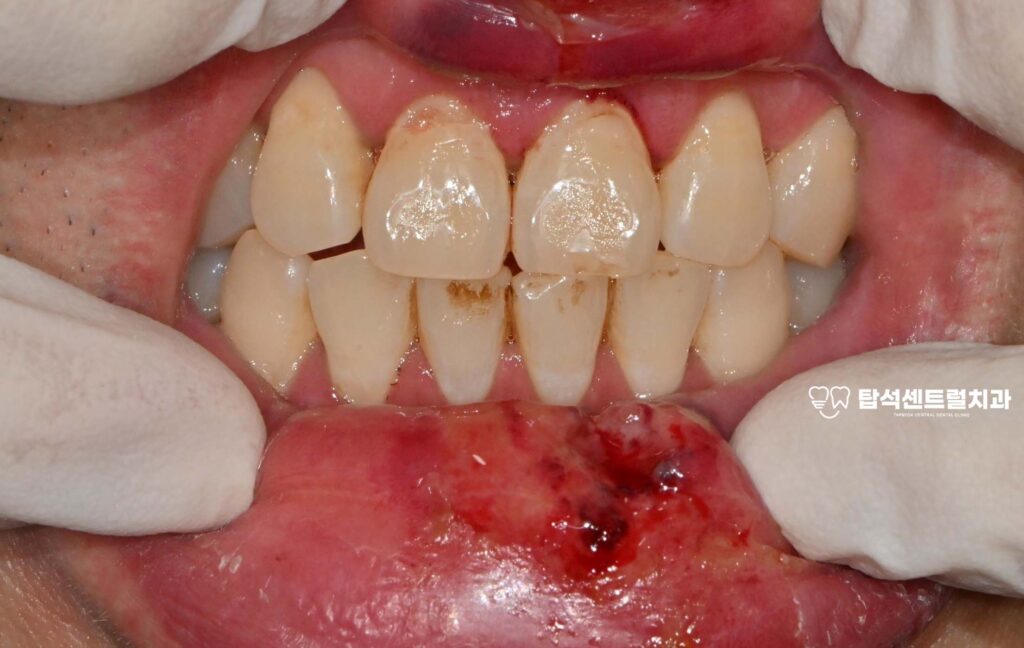

빙판길 낙상 사고가 발생하면

위아래 입술에 찢어진 상처가

생기는 경우가 많습니다.

또한 상악 중절치라고 불리는

윗쪽 앞부분에 금이 가거나

뿌리 부분까지 다칠 수 있습니다.

엑스레이나 CT 촬영을 통해

내부 상태를 정밀하게 확인하게 됩니다.

육안으로는 보이지 않는

미세한 균열이나 뿌리 골절을

영상 검사로 파악할 수 있습니다.